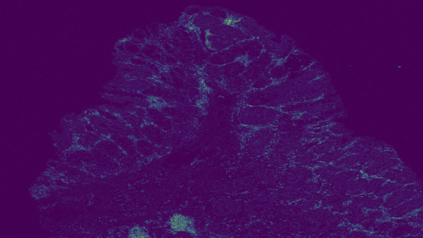

The usage of chemical imaging technologies is becoming a routine accompaniment to traditional methods in pathology. Significant technological advances have developed these next generation techniques to provide rich, spatially resolved, multidimensional chemical images. The rise of digital pathology has significantly enhanced the synergy of these imaging modalities with optical microscopy and immunohistochemistry, enhancing our understanding of the biological mechanisms and progression of diseases. Techniques such as imaging mass cytometry provide labelled multidimensional (multiplex) images of specific components used in conjunction with digital pathology techniques. These powerful techniques generate a wealth of high dimensional data that create significant challenges in data analysis. Unsupervised methods such as clustering are an attractive way to analyse these data, however, they require the selection of parameters such as the number of clusters. Here we propose a methodology to estimate the number of clusters in an automatic data-driven manner using a deep sparse autoencoder to embed the data into a lower dimensional space. We compute the density of regions in the embedded space, the majority of which are empty, enabling the high density regions to be detected as outliers and provide an estimate for the number of clusters. This framework provides a fully unsupervised and data-driven method to analyse multidimensional data. In this work we demonstrate our method using 45 multiplex imaging mass cytometry datasets. Moreover, our model is trained using only one of the datasets and the learned embedding is applied to the remaining 44 images providing an efficient process for data analysis. Finally, we demonstrate the high computational efficiency of our method which is two orders of magnitude faster than estimating via computing the sum squared distances as a function of cluster number.